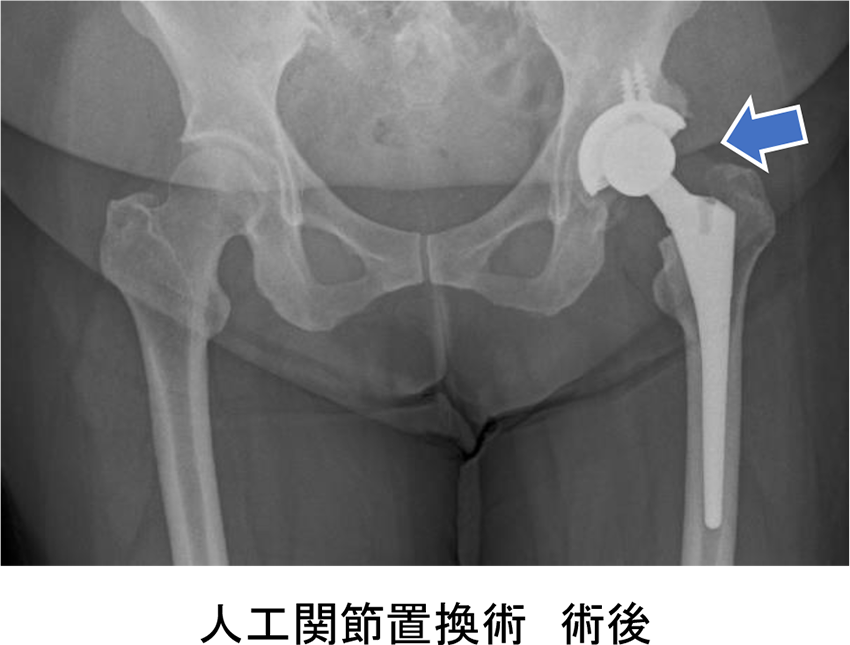

【治療は?】 ■保存療法

【手術は怖くない?リスクは?】 人工関節置換術では、術後脱臼を予防するために禁止肢位(正座から足をくずした座り方、いわゆる女の子座りのような姿勢がダメなど)がありますが、これも近年筋肉や腱をできるだけ切らない手術法が普及し、より制限なく日常生活に戻っていただけるようになっていきます。 患者様はそれぞれ症状も違えば生活様式も異なります。私たちは患者様一人一人に合わせた治療法を提案すべく日々の診療に取り組んでおります。股関節でお悩みのことがあればお気軽にご相談ください。 |